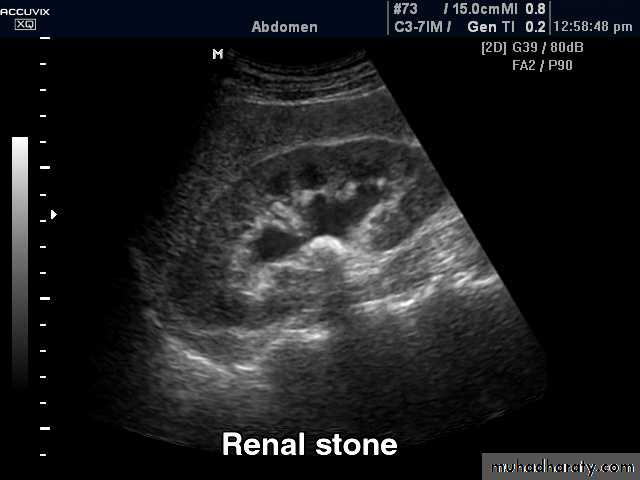

Most renal calculi of more than 5 mm are usually seen at US but smaller size calculi may be missed. Stones regardless of their consistency produce intense echoes and cast acoustic shadows.

Stones in the ureters cannot be excluded by US , so IVU or CT is indicated

Stones in the VUJ and bladder are well demonstrated by USCT when performed without contrast is sensitive for detection of all types of stones